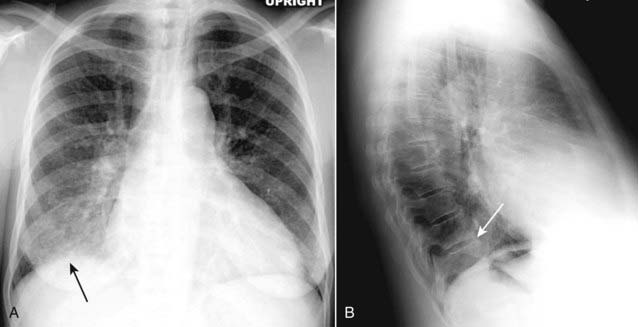

image

Figure 7-11 The spine sign.

Frontal (A) and lateral (B) views of the chest demonstrate airspace disease on the lateral projection (B) in the right lower lobe that may not be immediately apparent on the frontal projection (you can see the pneumonia in the right lower lobe in (A) (solid black arrow). Normally, the thoracic spine appears to get “blacker” as you view it from the neck to the diaphragm because there is less tissue for the x-ray beam to traverse just above the diaphragm than in the region of the shoulder girdle (see also Fig. 2-3). In this case, a right lower lobe pneumonia superimposed on the lower spine in the lateral view (solid white arrow) makes the spine appear “whiter” (more dense) just above the diaphragm. This is called the spine sign.